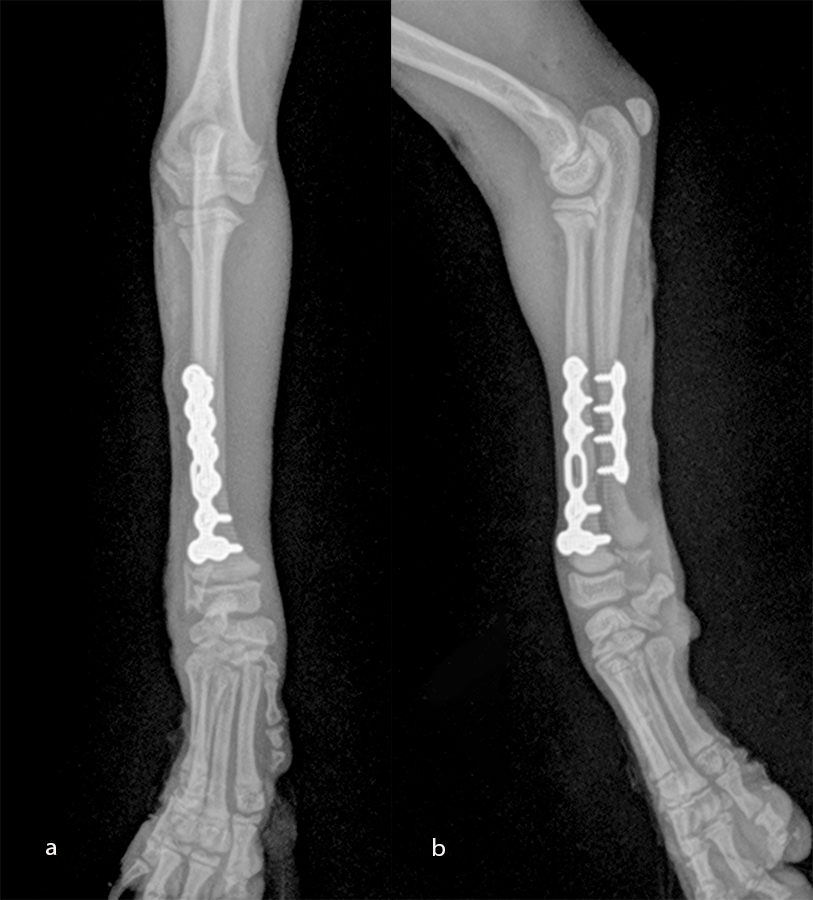

Open reduction and internal fixation of distal radial and ulna fractures with a single 1.3 radial plate (Fig 6).

An open but do-not-touch approach was performed, and the plate was fixed with one proximal and one distal cortex screws and one proximal and one distal locking screws (Fig 8). After 1 month the fracture of the radius was healed, and the dog had a complete functional recovery (Fig 9).